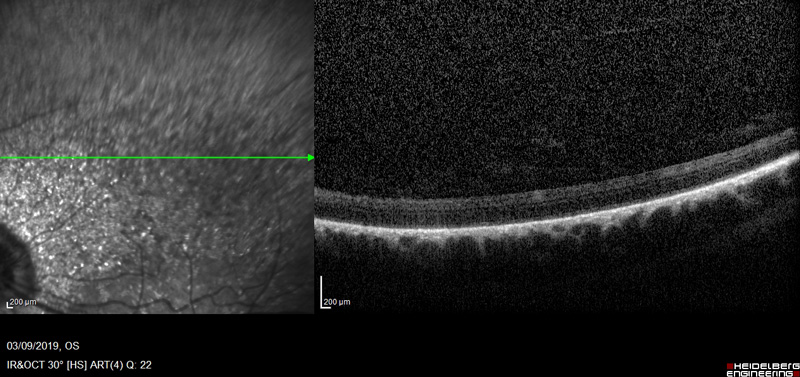

- OCT fondo ocular

Se le practicó también una OCT del fondo ocular que determinó que padecía una degeneración de retina y excavación del nervio óptico en el ojo afectado por glaucoma.

El aumento de la presión intraocular lo primero que provoca son lesiones en el nervio óptico, pero en algunos casos como en el de Riky también está gravemente afectada la retina.